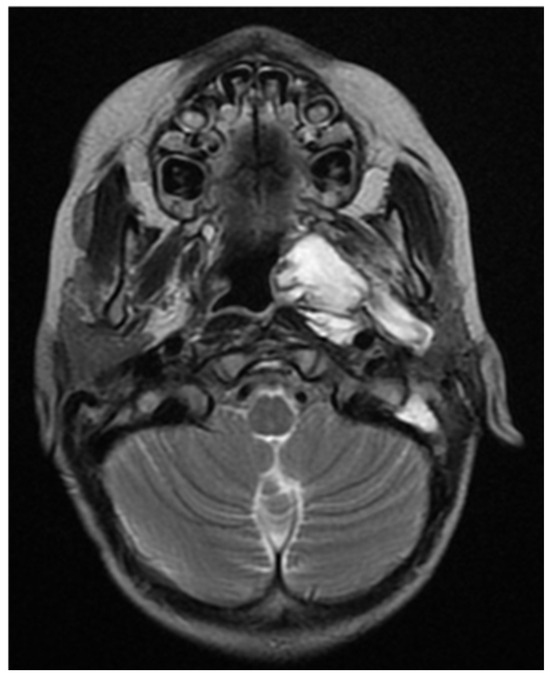

The restating MRI before the fourth chemotherapeutic block showed persisting tumor mass in the nasopharynx and oropharynx with reduced size in the different dimensions 15/44 mm axial size and 31/40 mm coronal size. The lesion involves the vascular nerve bundle in the area of the cavernous sinus. In the skull base area, the formation was closely adjacent to the internal carotid artery. Full morphologic response to the cervical lymph nodes. (Figure 9, Figure 10 and Figure 11).

Figure 9. MRI on the 4th month from the start of chemotherapy.

Figure 10. MRI on the 4th month from the start of chemotherapy.

Figure 11. MRI on the 4th month from the start of chemotherapy.